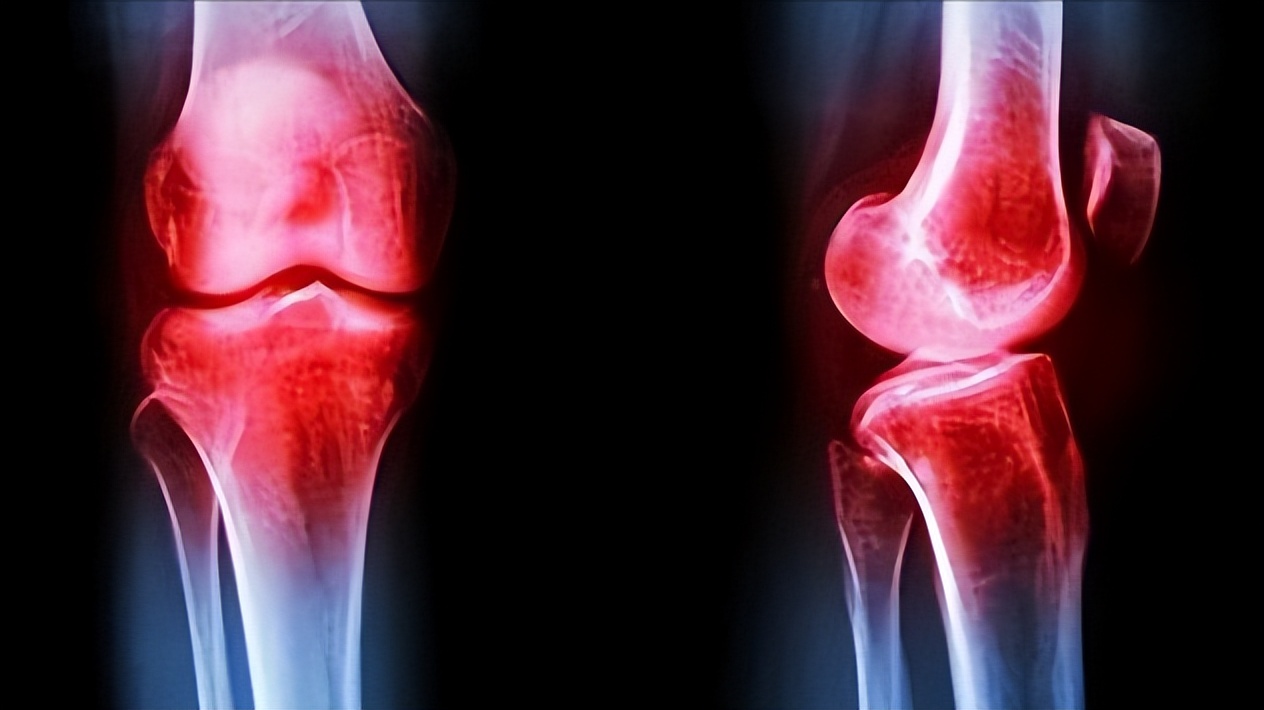

其实老王的朋友说的没错,老觉得关节疼痛僵硬,确实可能是骨关节炎所致。这是在中老年人非常常见的一种疾病,65岁以上膝关节疼痛的人中,有一半都是骨关节炎患者。像我们常说颈椎病、骨刺、骨质增生等都属于骨关节炎的范畴。

而骨关节炎的临床表现就是关节疼痛、关节活动受限,这是因为没有了软骨的保护,我们在走路的时候骨头与骨头之间会相互摩擦,可是骨头最外边的骨膜、周围的滑膜上的神经是非常丰富的,长此以往就会觉得非常疼痛。

其中关节疼痛初期为间断性的疼痛,等到休息后会有所好转,而关节活动受限常见于髋关节、膝关节,晨起后会出现僵硬的感觉,这也是为什么老年人总会觉得关节疼痛僵硬。